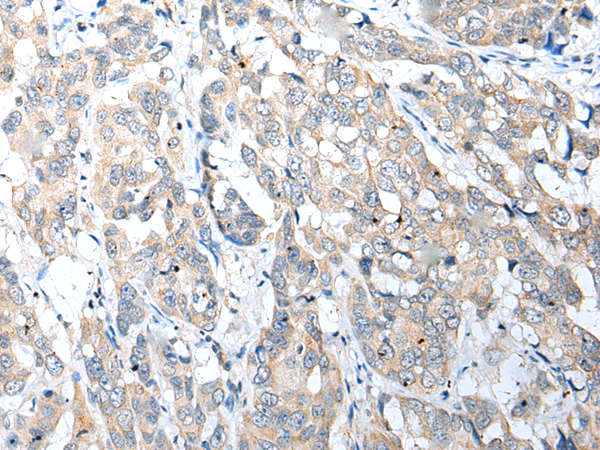

分类: 科研抗体货号: P02152别名: ED3; EDA3; ECTD11A; ECTD11B应用: IHC反应种属: Human